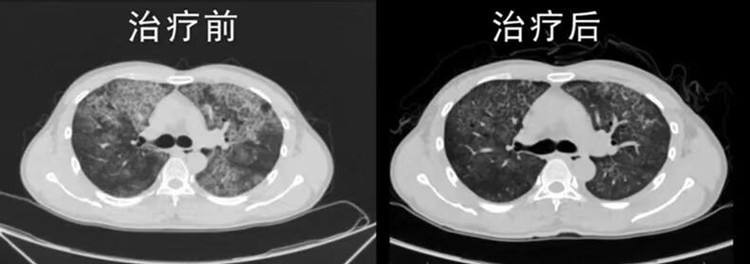

图说:治疗前后胸部CT比较

术后患者生命体征平稳,第二天患者即可下地行走,自觉呼吸困难明显改善,尝试着从1楼步行上了10楼的呼吸内科,中途仅在6楼休息一次,身体状况转好。